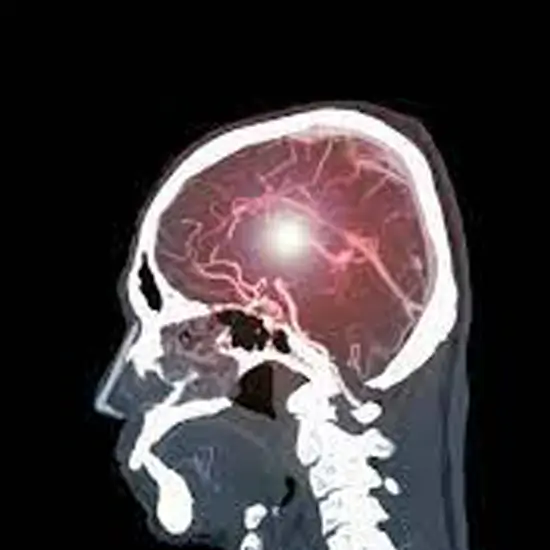

CT Head & Neck Angio is an imaging procedure that obtains pictures of the flow of blood in the blood vessels in the head and neck. This scan is used to view the large arteries in the neck that lead to the brain and the veins/ the four arteries that carry blood to the brain. It helps in finding the bulge in a blood vessel and narrowing or a blockage in a blood vessel that slows the blood flow.

CT Head & Neck Angiography is an imaging diagnostic tool that uses X-rays with the computer to detect disorders and diseases related to the blood vessels of the neck and head and surrounding area. Patients should not avoid any symptoms related to blood vessels of neck and head abnormalities or disorders. Patients should go for screening to avoid any delay in diagnosis and treatment of the blood vessels of neck and head abnormalities.